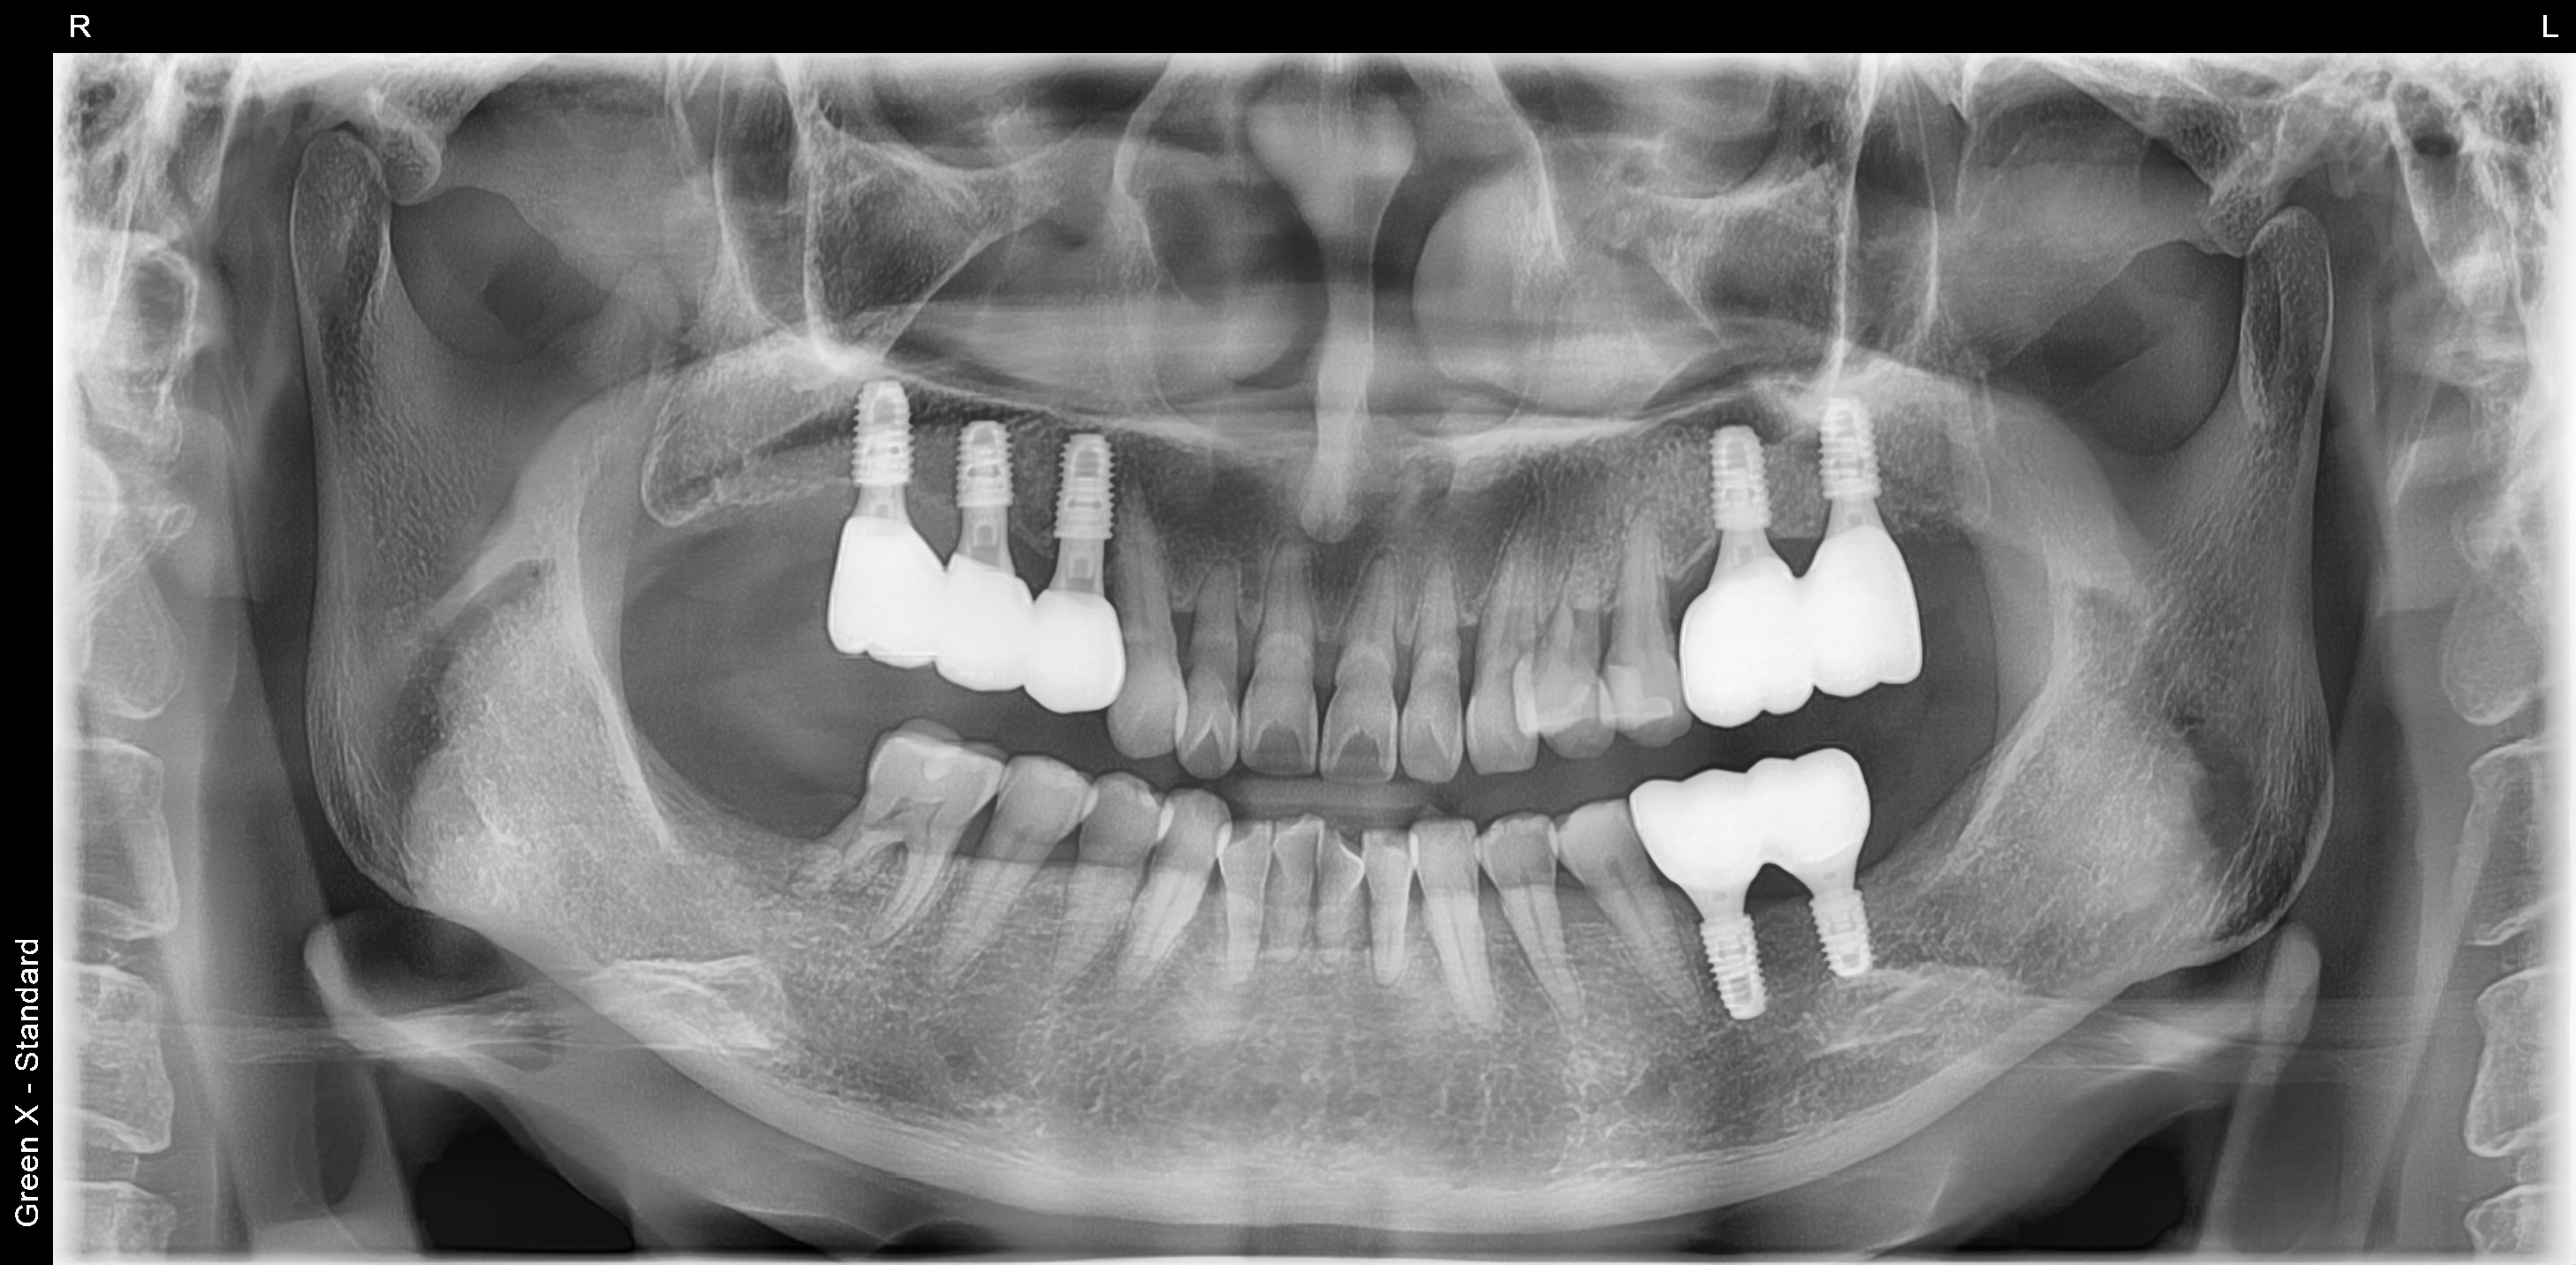

오른쪽(사진상 왼쪽) 위 4개의 어금니 발치 후 3개 임플란트 식립

왼쪽 위(사진상 오른쪽) 위 2개의 어금니 발치 후 2개 임플란트 식립

왼쪽 아래 2개의 임플란트 식립.

모든 임플란트는 네비게이션을 이용하여 식립했습니다.

<치료 후>